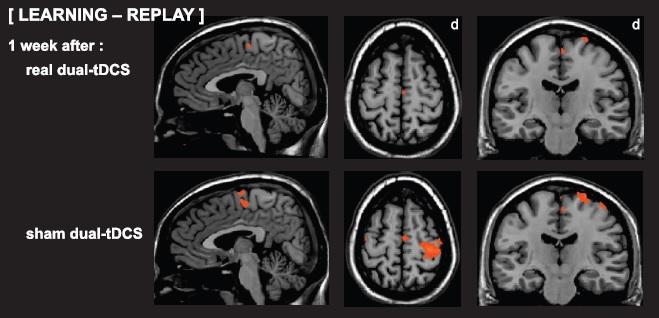

Thanks to functional MRI, this second study demonstrates that the combination of motor learning and non-invasive cerebral stimulation improves the efficiency of the cerebral activity. Indeed, one week after the placebo stimulation, the cerebral activations measured via the functional MRI was very diffuse. Large cerebral zones were somehow « recruited » although motor performance was low (poor retention). On the other hand, one week after real stimulation, the cerebral activation was focussed on the essential motor zones, almost identical to a person without stroke-impact although the motor performance was significantly better (enhanced task retention). In other words, the combination of motor learning and tDCS reinforced the essential motor zones and this specific network was reactivated one week after the real intervention.